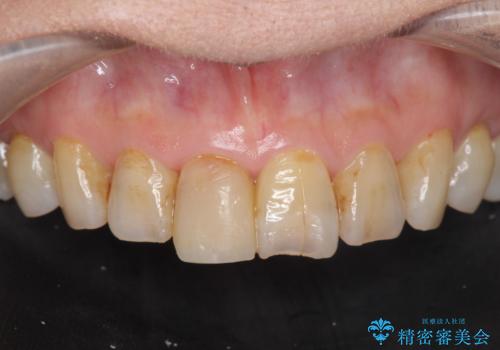

- 前歯を転倒で受傷し、審美性の回復を求めて来院されました。

近医で暫間的なコンポジットレジン修復が為されていましたが、色調に不満があるということでした。

色調の変化が少なく、長期的な予後を見込めるジルコニアクラウンで天然歯を模した審美性の回復を計画します。